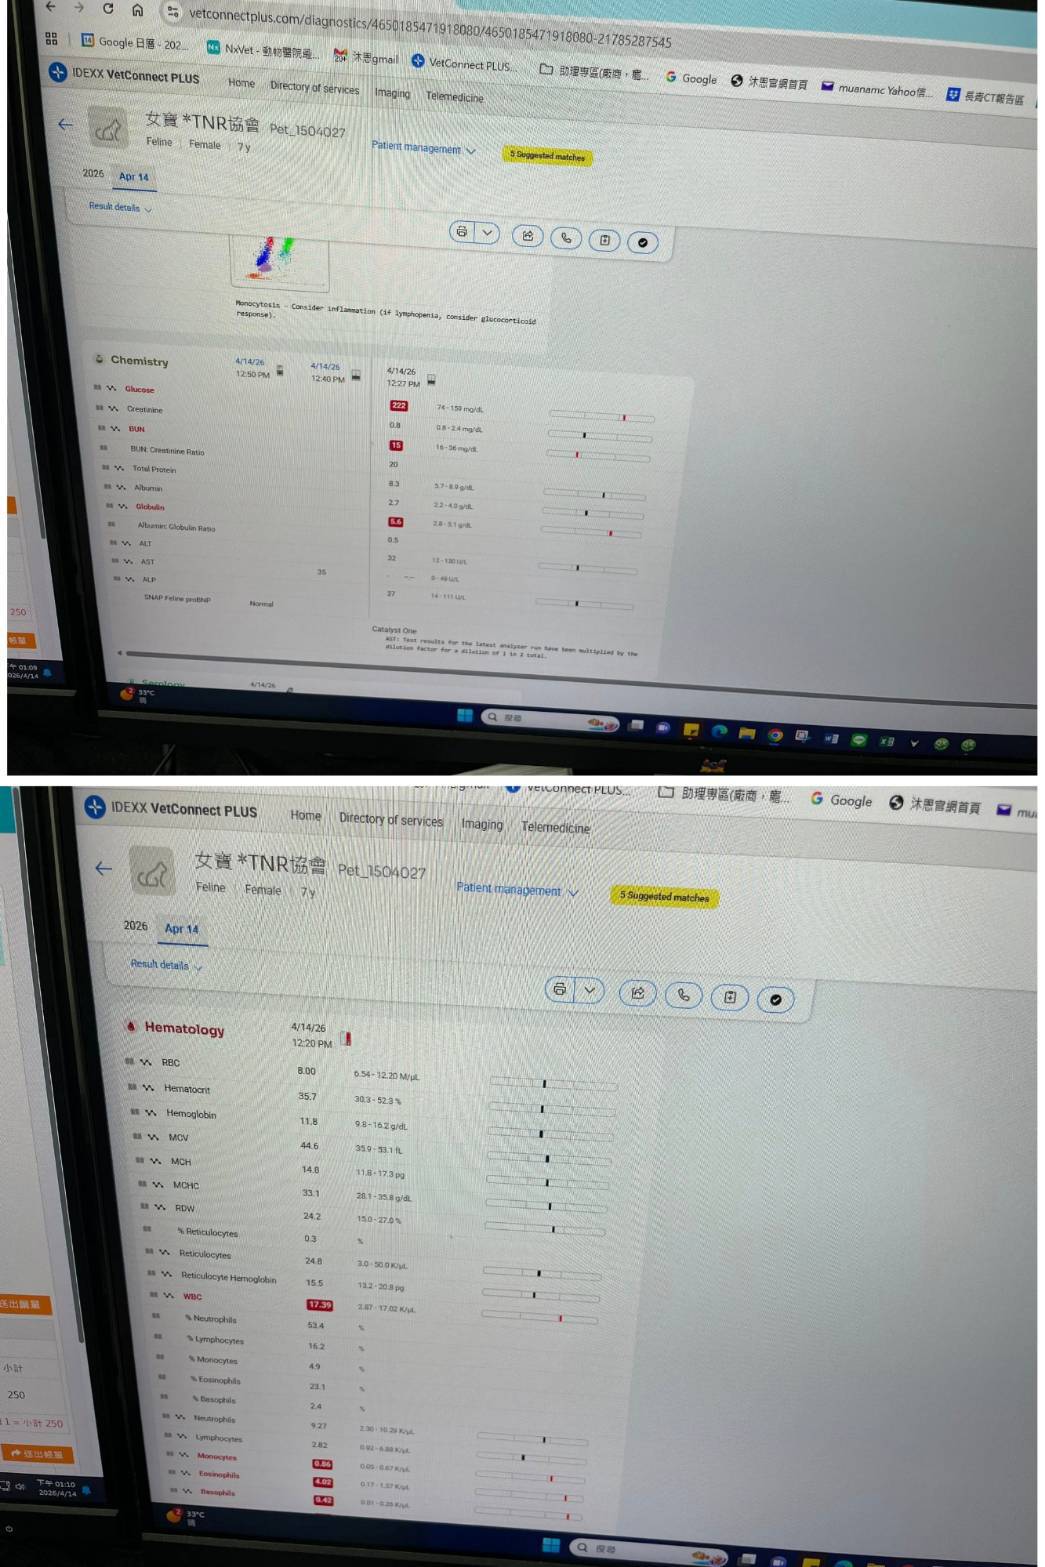

候補人員: 因考慮無人遞補、轉匯收費、信用卡刷卡匯率、寄送收據與郵資等成本,每筆醫助人數將斟酌彈性增加1-5位名額。 動物病情說明: 女寶為汐止愛媽餵養之貓咪,已在汐止照顧五~六年也已結紮,研判已有七歲左右。後於2026年4月發現女寶毛髮日漸稀疏,擔心女寶可能有健康問題,因此聯繫協會協助誘捕看醫,後經協會義工於2026年4月15日順利誘捕並帶往沐恩醫院就醫檢查,經血檢檢查後,可能不只七歲應有10歲左右且無晶片,心絲蟲、白血、愛滋都陰性。毛髮稀疏因疑似寄生蟲導致皮膚發炎反應,先吃驅蟲藥再觀察。

經X光檢查發現右前肢骨骼退化較嚴重,左邊也有一點骨骼退化;肺功能也是偏差;有牙周炎、牙齦萎縮所以齒根比較出來。X光有拍到兩顆東西,穿刺抹片檢查,淋巴細胞正常,淋巴結腫大。於醫院先點一錠除,並開立內用驅蟲藥,三個月後體外驅蟲需要再做一次。目前已於14日當日就醫後先行安置於協會幾日,因考量女寶年齡已大,汐止愛媽會帶回家中安置給女寶一個長久安穩的家。本筆醫助是女寶2026年4月14日於沐恩醫院看診的費用,包含血檢、X光、三合一、心臟快篩、皮膚抹片、一錠除滴劑及驅蟲藥。

心絲蟲、白血、愛滋都陰性。